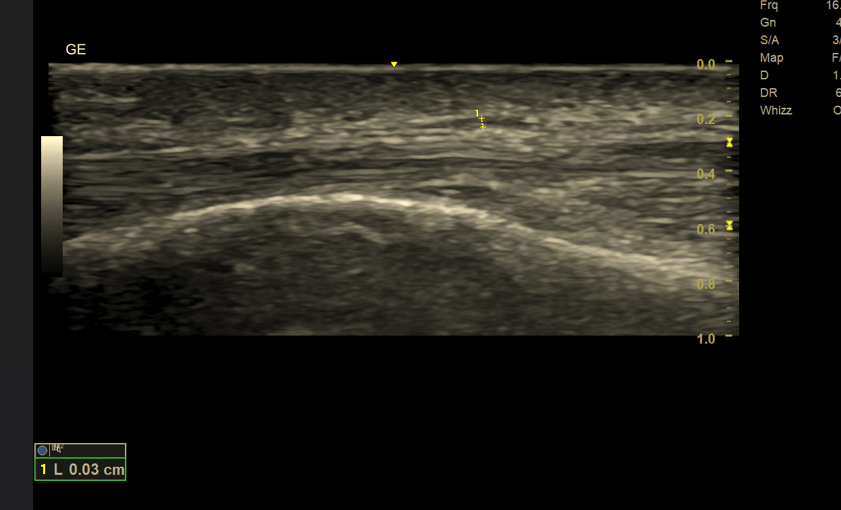

👉 Nerwy cienkie (< 3 mm) – diagnostyka praktycznie wyłącznie za pomocą USG wysokiej rozdzielczości

Nerwy cienkie (< 3 mm) – tylko USG wysokiej rozdzielczości

Dlaczego MR nie sprawdza się w ocenie cienkich nerwów?

Rezonans magnetyczny, mimo doskonałego kontrastu tkanek miękkich, nie oferuje wystarczającej rozdzielczości przestrzennej, aby wiarygodnie zobrazować bardzo cienkie struktury nerwowe.

➡️ USG zapewnia:

- rozdzielczość sięgającą 0,1–0,2 mm

- możliwość oceny fascikularnej budowy nerwu

- obrazowanie dynamiczne (ruch, ucisk, prowokacja objawów)

1. Rozdzielczość przestrzenna

- USG: zdecydowanie lepsza w ocenie nerwów cienkich i powierzchownych

- MR: ograniczona dla struktur < 3 mm

🔍 Wniosek: cienkie nerwy → tylko USG

Dlaczego USG jest lepsze od MR w ocenie cienkich nerwów?

USG oferuje znacznie wyższą rozdzielczość przestrzenną niż MR. Dzięki temu możliwa jest:

- ocena struktury pęczkowej nerwu,

- wykrycie pogrubienia, obrzęku lub ucisku,

- dokładna lokalizacja miejsca uszkodzenia.